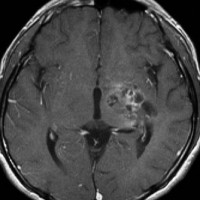

ICE化学療法投与開始から数日で小さくなります

この例は古いので第3脳室開窓術 ETV をしていません。左はICE化学療法前。中央は9日後。右は25日後です。閉塞性水頭症があっても1週間くらいで中脳水道が通って水頭症は改善します。ジャーミノーマであれば,ICE化学療法1コースでかなり縮小するはずです。このような顕著な効果がない時には,逆にジャーミノーマ以外の胚細胞腫瘍が混在していると考えた方がいいでしょう。多くは奇形腫の混在です。